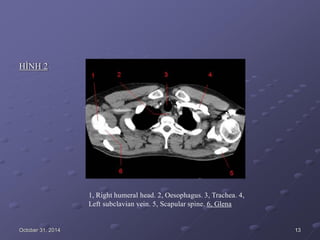

HÌNH 2

1, Right humeral head. 2, Oesophagus. 3, Trachea. 4,

Left subclavian vein. 5, Scapular spine. 6, Glena

October 31, 2014 13